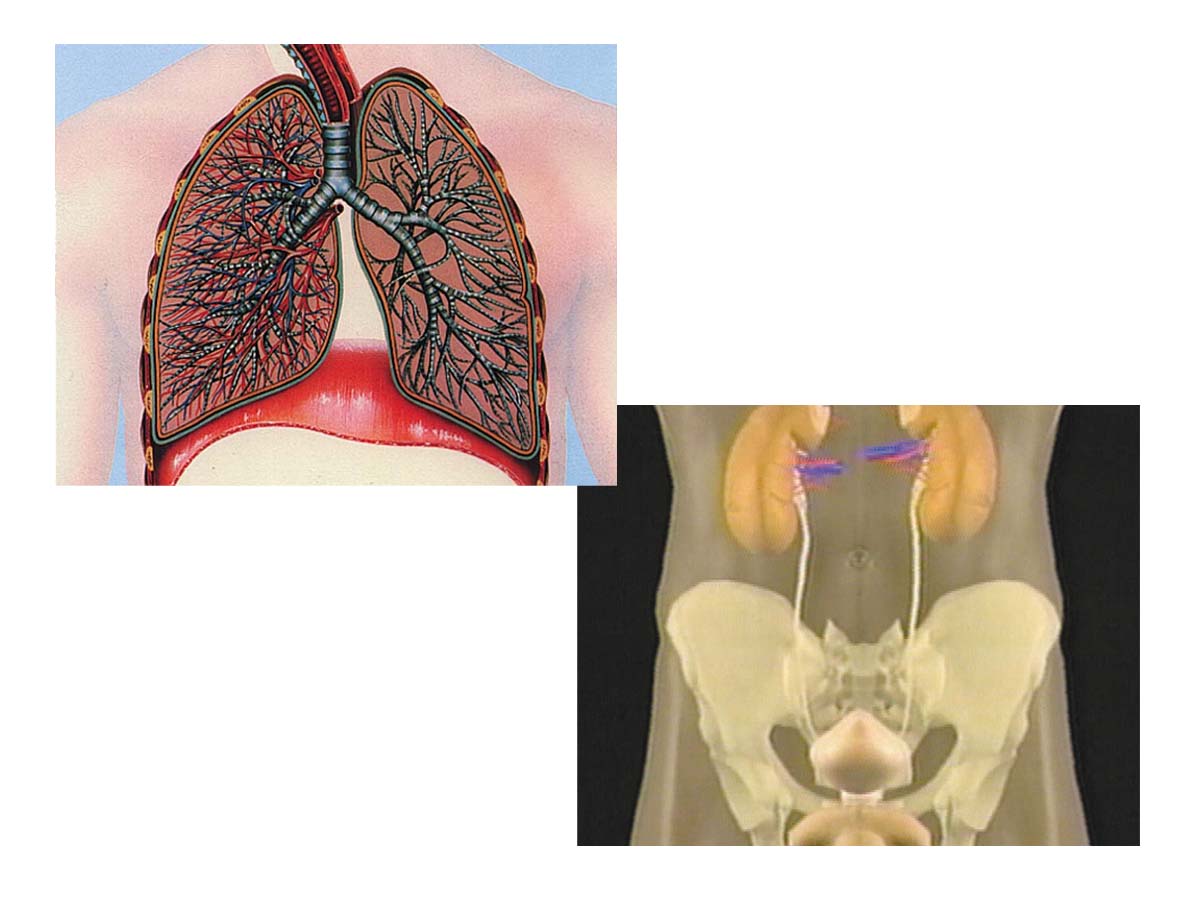

Das Exkretionssystem hat die Aufgabe, Abfallprodukte aus dem Organismus zu entfernen. Das wichtigste Organ dieses Systems ist die Niere, die das Blut filtert und den Urin bildet. Die Lunge, die Leber und die Haut sind weitere Organe, die zum Exkretionssystem zä hlen.

Dieser Film erläutert die Bedeutung der Exkretion und die Funktion der einzelnen Organe. Dabei wird auch deren enge Zusammenarbeit mit anderen Organsystemen wie etwa dem Kreislaufsystem deutlich.